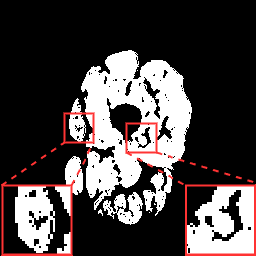

Finally, we define the set of corrected pseudo-labels as the intersection between the and masks. Examples are shown in Fig. 2.

(a) Image

(b)

(c)

(d)